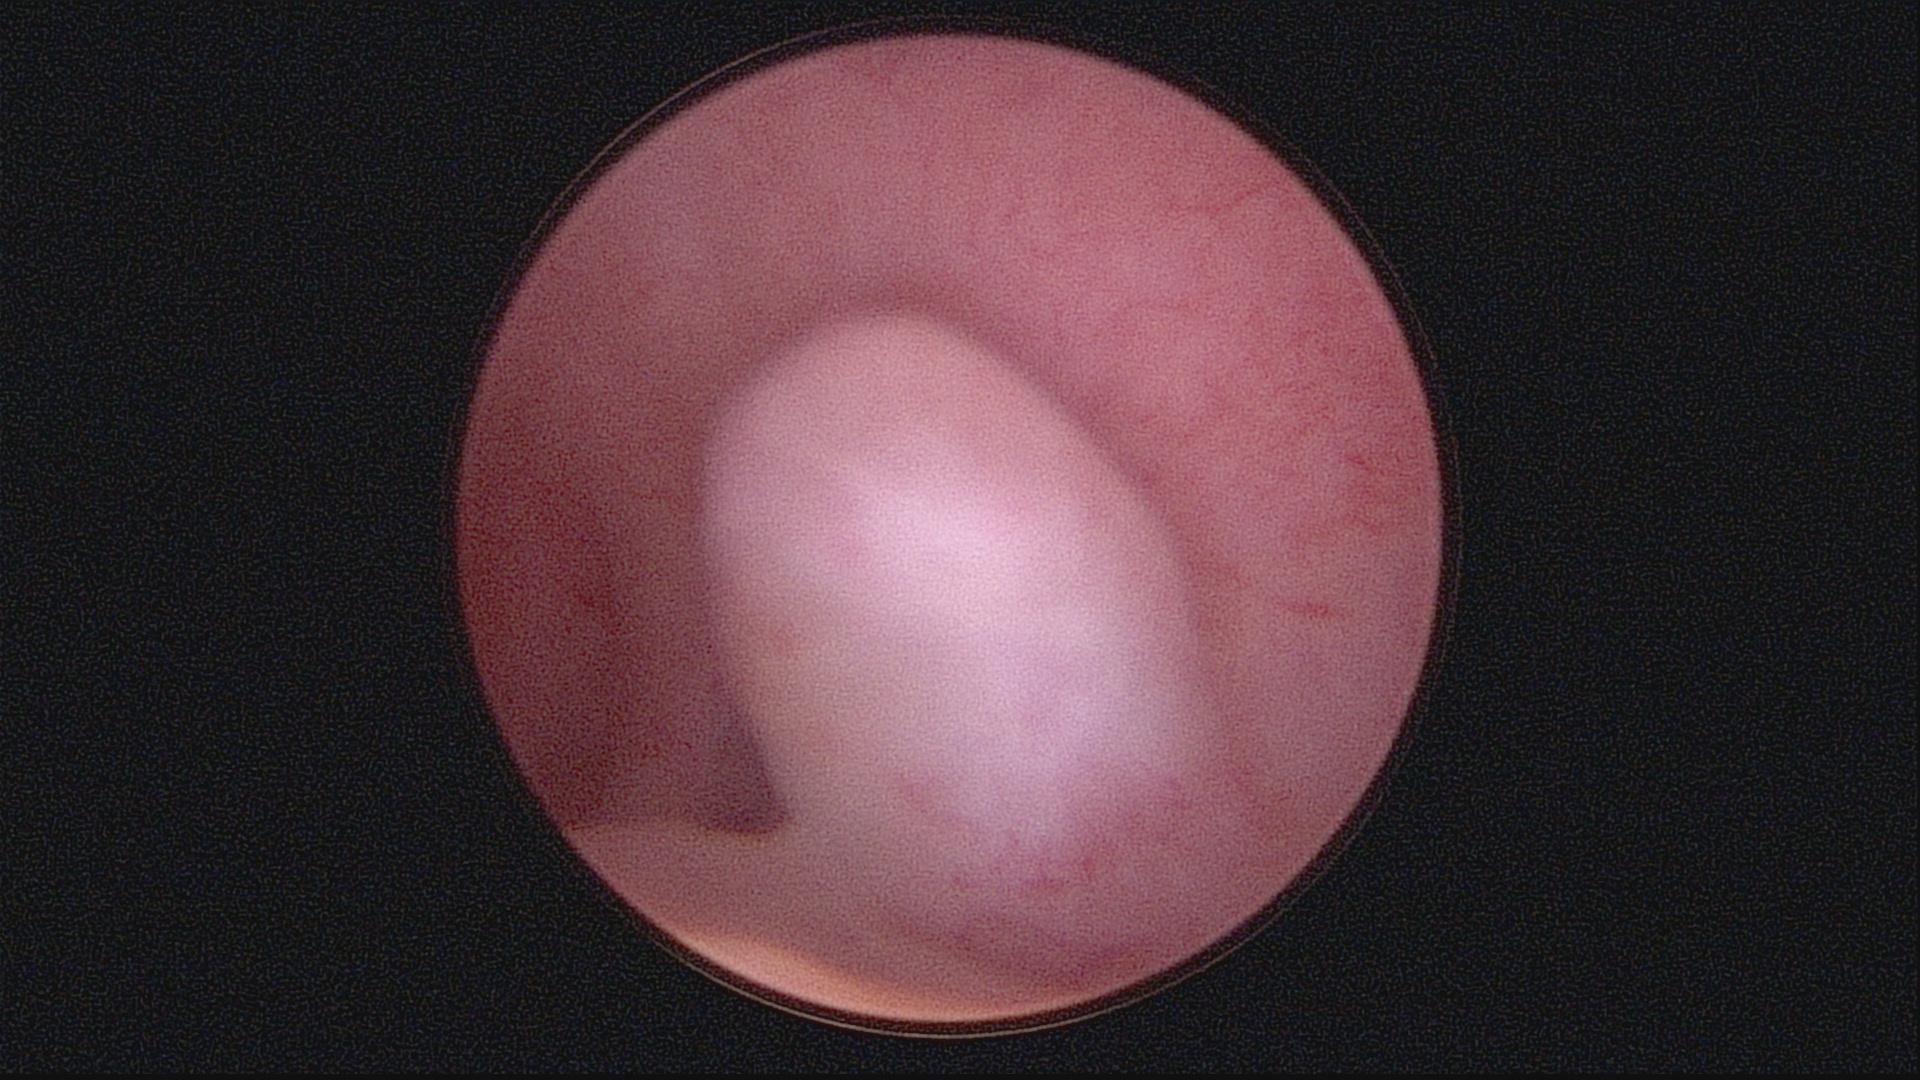

子宫内膜癌宫腔图片

注:月经异常的广大 妇女及时 就诊!!!